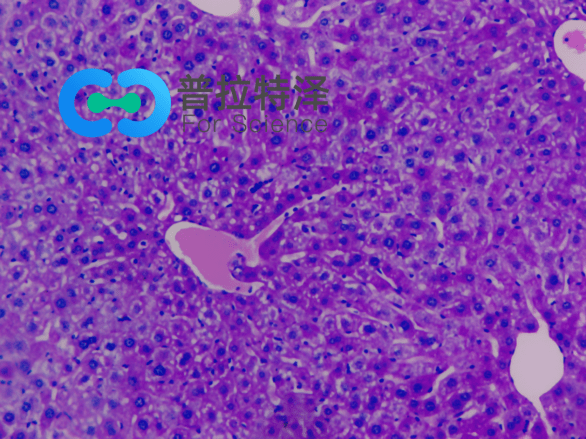

在生物學和醫學領域,PAS染色(Periodic Acid-Schiff Stain)是一種常用的組織染色技術,用于檢測組織中的多糖類物質,如糖原和粘多糖。掌握PAS染色的正確步驟,對于科研人員和醫學工作者來說至關重要。普拉特澤生物——組織染色實驗平臺操作各類組織的染色實驗上百例,專業代做PAS染色和各種染色實驗,本文將從入門到精通,全面介紹PAS染色的步驟和注意事項。

→Schiff試劑染色:將氧化后的切片放入Schiff試劑中,醛基與Schiff試劑中的亞甲基藍發生反應,形成紫紅色產物。